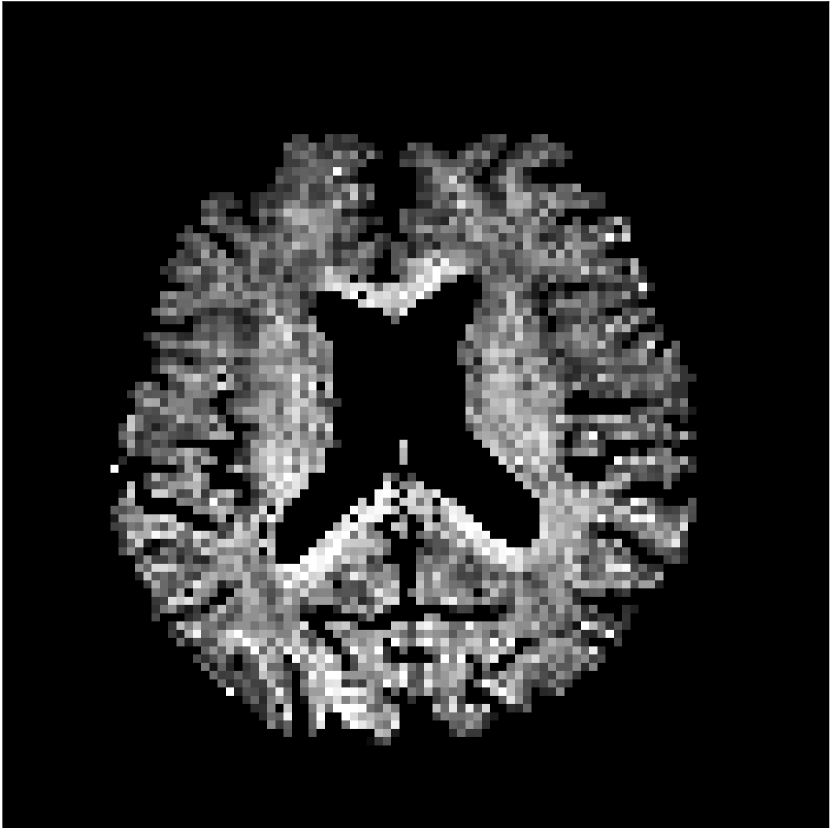

Figure 10 compares mean diffusivity maps across various partial Fourier factors between the CCNN and state-of-the-art methods.

No PF

7/8 PF

6/8 PF

5/8 PF

SoA

MD, μ𝜇\mum2/ms

CCNN

Figure 10: Comparison of mean diffusivity (MD) parameter maps across PF factors of 5/8ths, 6/8ths, 7/8ths, and without PF (No PF). The methods include state-of-the-art (SoA) and CCNN methods. Without partial Fourier, both methods are similar; however, as the PF factor increases, substantial artifacts are introduced in the SoA method, particularly around the lateral ventricles. The CCNN method is able to reduce the introduction of artifacts.

The methods perform similarly without partial Fourier acceleration, but as partial Fourier acceleration increases, the image is continually degraded in the SoA method, with "black voxels" appearing around the lateral ventricles. The CCNN method mitigates the appearance of these artifacts in the parameter maps.